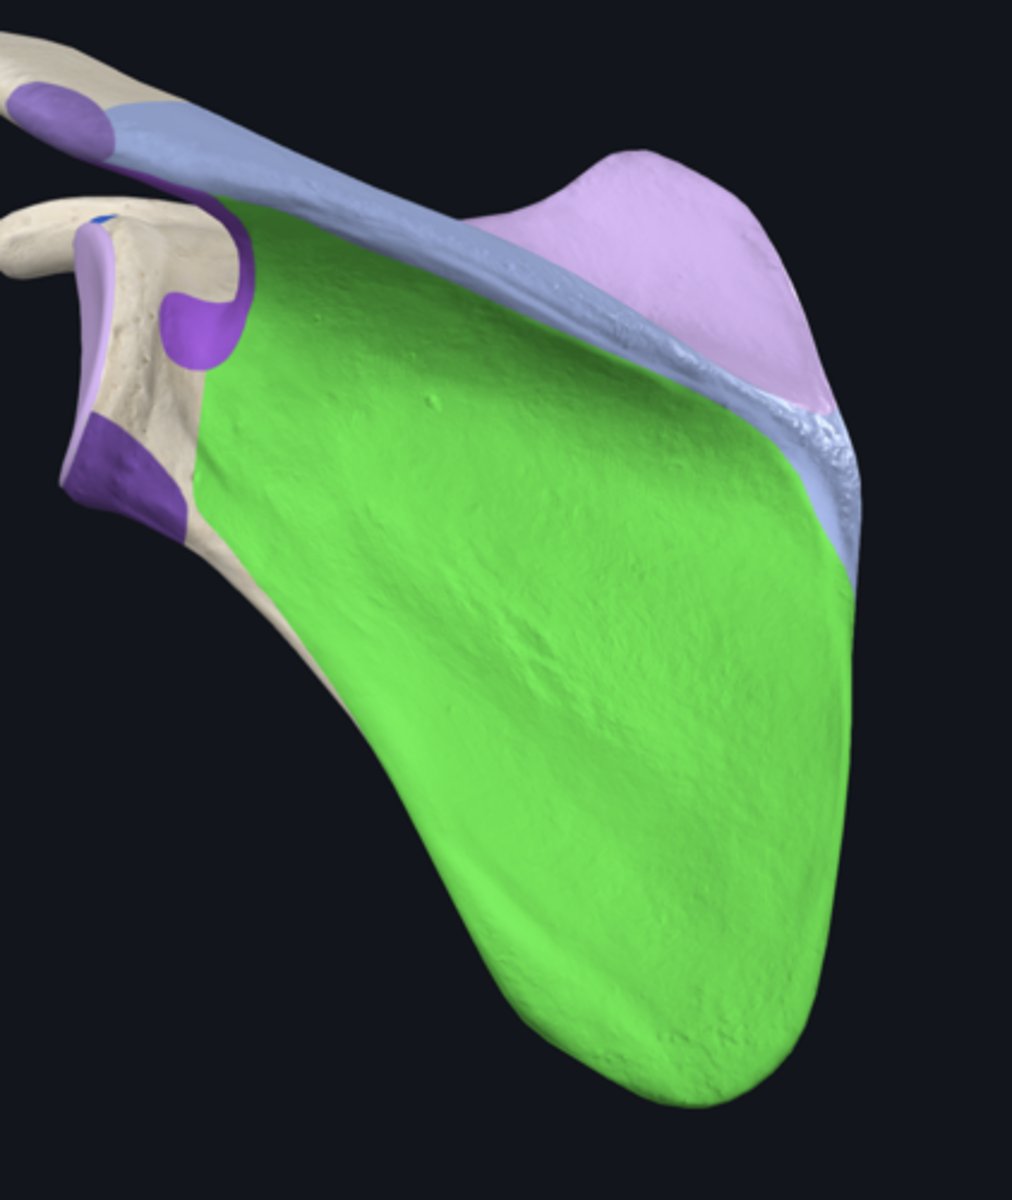

Superior angle of scapula

lateral border of scapula

medial border of scapula

inferior angle of scapula

body of scapula

costal surface of scapula

posterior surface of scapula

infraspinous fossa

subscapular fossa

supraspinous fossa